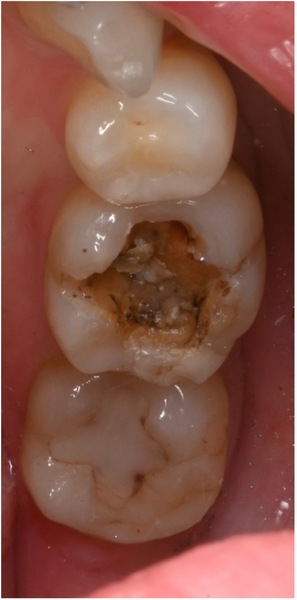

銀歯の下は写真のようになっていました。

穴から虫歯が進行しています。

キャラメルやお餅などで取れてしまう銀歯の中もこうなっていることがしばしばあります。